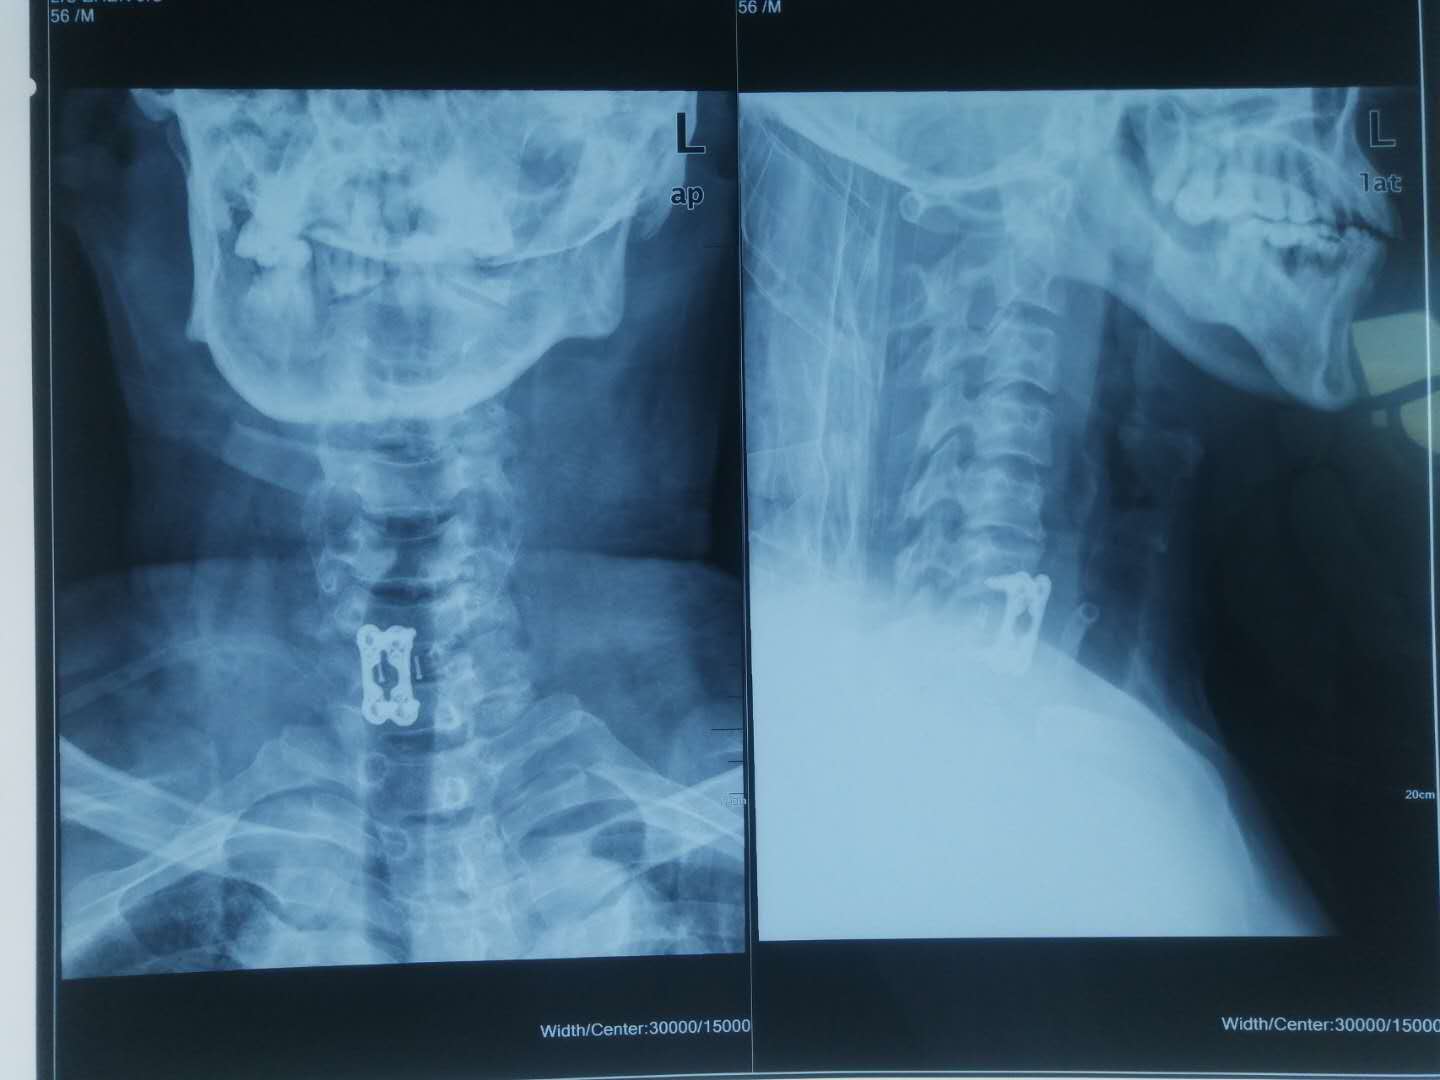

经CT显示,刘师傅胸部左侧肋骨多处骨折、肺部挫裂伤、颈部六七颈椎骨折脱位伴不完全瘫痪,“钢铁脊梁”组组长主任医师刘涛立即立即联系手术室备台,同时打电话叫来脊柱团队组员副主任医师张运动、住院医师张治河、住院医师王继龙,当天连夜为刘师傅进行“颈椎前路骨折脱位切开复位颈椎间盘切除椎间植骨融合CAGE植入椎管减压钛板前路固定术”。

手术从晚上11点一直持续凌晨3点,术后,刘师傅双上下肢刺痛症状减轻,肌力有所恢复,一周后,刘师傅双上下肢刺痛感基本消失,肌力恢复7成左右。由于刘师傅当时身体多处受伤,多部位同时手术明显不现实,不但术中术后患者体位无法摆放,多部位开放创口对机体也是相当大的损害。“家有三件事,先从紧处来”,等 刘师傅颈椎受限解除后,胸心外科主任王洪波、骨科主任医师刘涛联合为刘师傅进行胸部手术。两周后,刘师傅总体恢复情况良好,双上下肢肌力已基本恢复,带着支具便可下地走路。